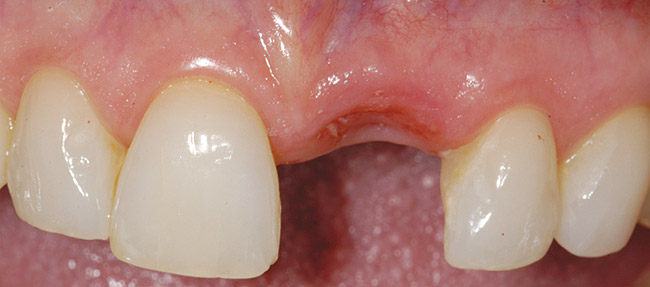

A 54-year-old woman was referred for treatment of a fractured maxillary right lateral incisor, secondary to recurrent subgingival decay. Clinical and radiographic examination revealed a high smile line; a thin, highly scalloped biotype; class II deep bite; a thin labial plate (< 2mm) with 4 mm of vertical bone loss; and class I interproximal height of bone24 (Figure 9 and Figure 10).

Figure 9  Failing maxillary right lateral incisor with root fracture and subgingival caries.

Figure 9

Figure 10  Periapical radiograph of the maxillary right lateral incisor with root fracture.

Figure 10